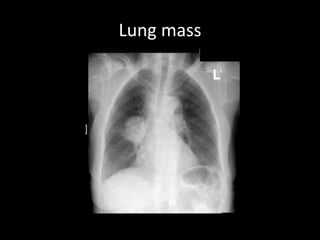

Lung mass